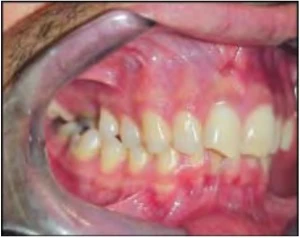

Hình 5. Răng cối lớn nghiêng gần chiếm nhiều khoảng trống hơn, dựng trục răng cối phía sau giúp tạo lại khoảng

Tạo khoảng trong chỉnh nha, các răng sau bị nghiêng luôn chiếm nhiều khoảng trống hơn. Các răng cối lớn có khuynh hướng nghiêng gần khi răng cối sữa thứ hai bị mất sớm hoặc bị sâu răng ở mặt xa không được phục hồi vào thời điểm thích hợp hoặc có bờ viền miếng trám chưa tốt. Mọc chậm răng cối nhỏ thứ nhất hoặc thứ hai cũng khiến cho răng sau nghiêng gần.

Dựng trục răng cối lớn có thể tăng độ dài cung răng từ 1-1.5mm. Các khí cụ cố định lý tưởng được dùng cho mục đích này. Các khí cụ hoặc vít tạo khoảng khác nhau cũng được dùng thường xuyên. Lip bumper và biến thể của nó cũng có thể mang lại kết quả tốt.